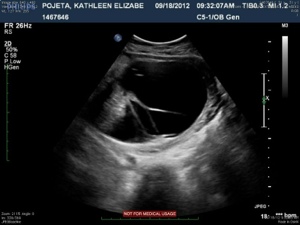

20120921-213507.jpg

The next four images just show various views of the strands/septations that are visible within the sac.